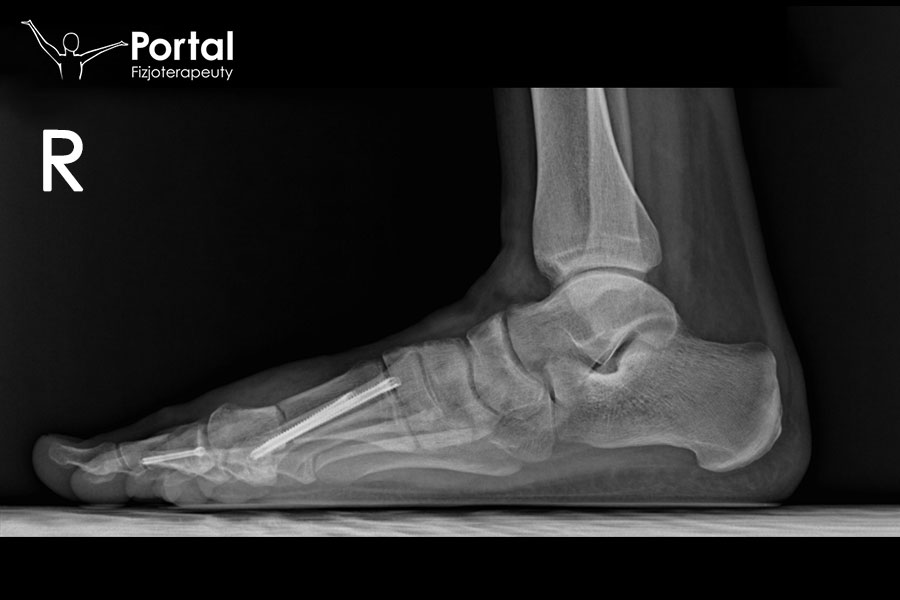

Ustawienie kości w pozycji skorygowanej stabilizuje się 2 tytanowymi śrubami przeznaczonymi właśnie tej metodzie. Śruby umieszcza się w kości na przyśrodkowo-grzbietowej stronie stopy. Trójpunktowe oparcie śruby proksymalnej (korówka przyśrodkowa i boczna I kości śródstopia oraz jej odłam dalszy) gwarantuje bardzo dobrą stabilizację uzyskanej korekcji.